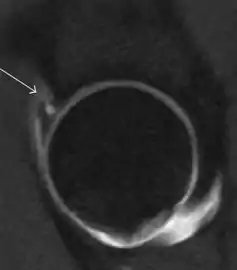

Figure 7:

Axial CT image of pigmented villonodular synovitis eroding the posterior cortex of the femoral neck.[1]

Sagittal T2* gradient echo image showing a posterior soft tissue mass with hypointense areas secondary to hemosiderin deposition.[1]

X-ray of synovial chondromatosis.[1]

CT of synovial chondromatosis.[1]

In synovial proliferative disorders, MRI demonstrates synovial hypertrophy. In the case of PVNS, characteristic foci of low signal intensity related to hemosiderin deposition are better seen on gradient echo T2* images (Figure 7). In the case of synovial osteochondromatosis, the synovial hypertrophy is accompanied by intermediate signal cartilaginous loose bodies and/or low signal calcified loose bodies.[1]